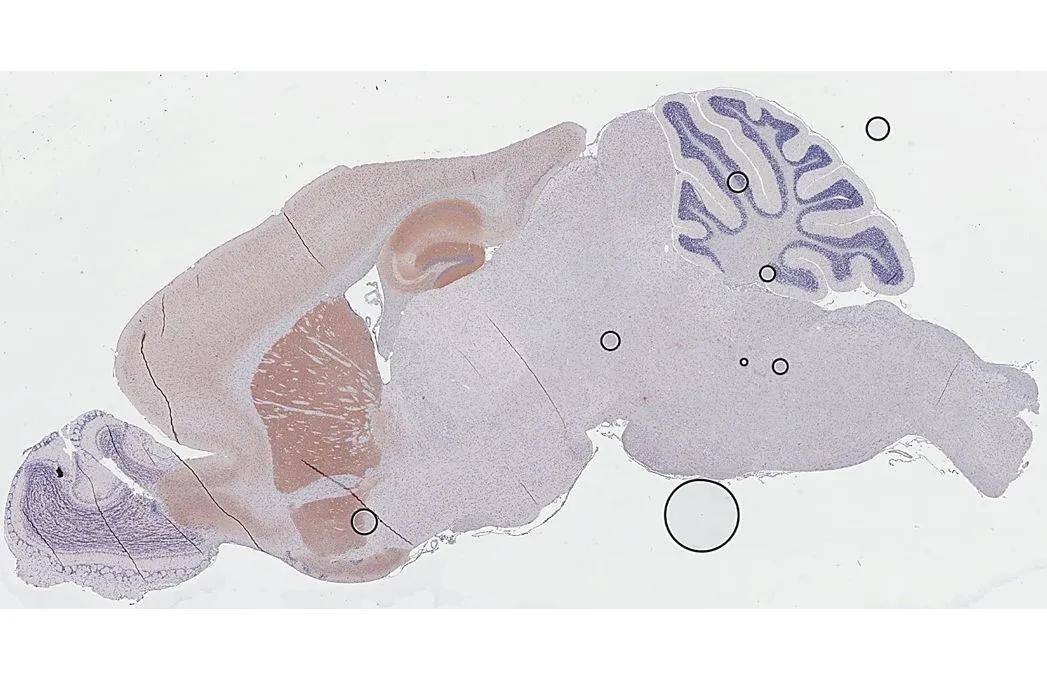

Immunohistochemistry-Paraffin: Muscarinic Acetylcholine Receptor M1/CHRM1 Antibody (HL3933) [NBP3-48854] -

Muscarinic Acetylcholine Receptor M1/CHRM1 antibody [HL3933] detects Muscarinic Acetylcholine Receptor M1/CHRM1 protein by immunohistochemical analysis.

Sample: Paraffin-embedded rat tissues.

Muscarinic Acetylcholine Receptor M1/CHRM1 stained by Muscarinic Acetylcholine Receptor M1/CHRM1 antibody [HL3933] (NBP3-48854) diluted at 1:200.

Antigen Retrieval: Tris-EDTA buffer, pH 9.0, 15 min